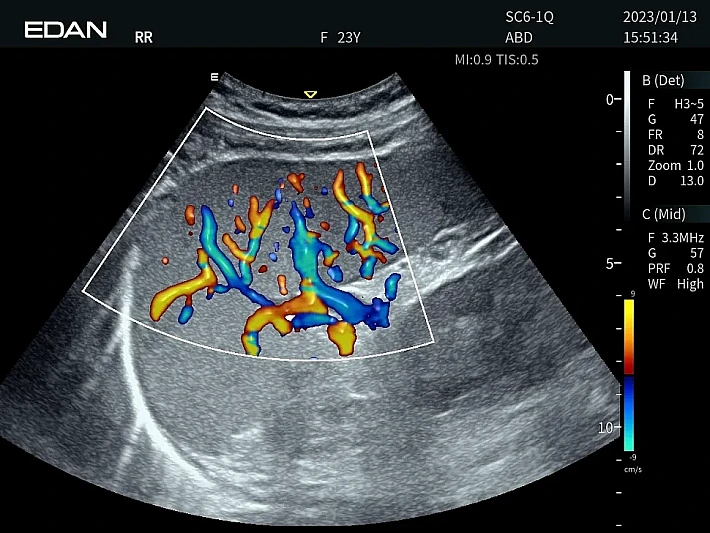

Медицинское оборудование и сервисное обслуживание